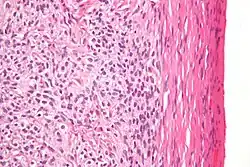

High magnification micrograph of a thecoma. H&E stain.

Microscopically, the tumour cells have abundant lipid-filled cytoplasm.